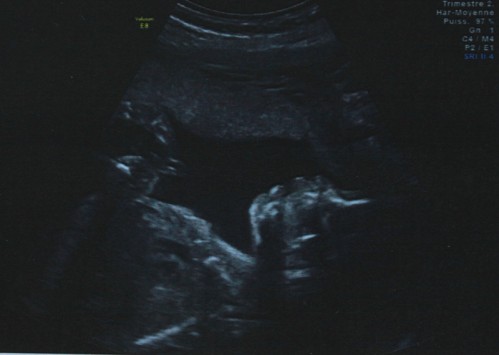

A peine arrivée dans son cabinet, je suis allongée et les premières images de bébé se sont affichées sur les écrans. Le coeur battant, la peur au ventre, j’attends que le médecin prononce ses premiers mots réconfortants avant de laisser à mon coeur la possibilité de s’apaiser. Les contrôles, les mesures se succèdent et le sourire reste sur les lèvres de l’échographe. Ses commentaires ne veulent pas toujours dire quelque chose pour nous… pas plus que les images parfois très abstraites. D’abord la tête en bas, bébé a joué les accrobates sous nos yeux, dévoilant des capacités motrices performantes : de beaux et rapides coups de pieds…

De la tête aux pieds, elle a effectué ses mesures avant de s’attarder sur son petit popotin et de nous révéler son sexe…

Bout de chou est une petite fille ! 🙂

En photo : notre petite puce !!! (ok c’est pas super net…)